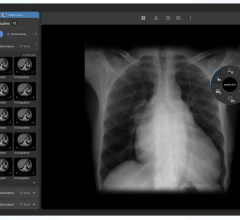

May 17, 2012 — Viztek announced an upgrade to its Opal-Ortho PACS (picture archiving and communications system) solution for orthopedic practices. The solution offers one single appliance that controls every aspect of orthopedics imaging, integrating the digital radiography (DR) or computed radiography (CR) solution and the PACS for optimal efficiency.

The Opal-Ortho suite is ideal for orthopedic practices of all sizes and allows them to grow without any additional hardware. It can house 100,000 imaging studies, enough for several years of continuous operation. Many practices currently utilize multiple appliances for PACS, CR/DR and electronic medical records (EMR) interfacing, and need to link them together to ensure each system can properly interface. This manual linking typically introduces complexity and possibility for errors.

In the upgrade, the suite’s digital templating was improved, and now provides physicians with immediate calculations to help them create more precise surgical plans before operating. It significantly streamlines the measurement process, allowing the physician to see more patients and reduce any possible operational delays. Another efficiency gain is found in the system’s automatic learning protocol, an intelligent feature that actively learns the doctor’s system usage patterns and allows them to perform key functions with less mouse clicks and fewer drag-and-drop actions.